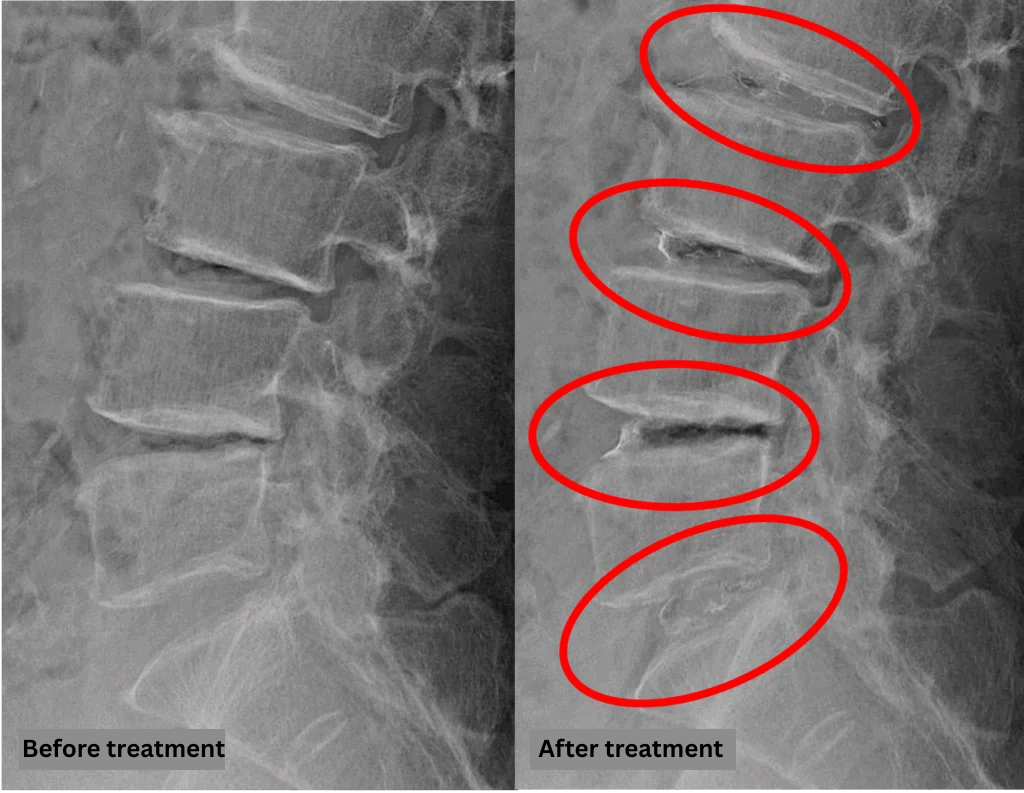

- L2/3, L3/4, L4/5: Disc degeneration, disc bulging, foraminal stenosis, status post-laminectomy

- L5/S1: Disc degeneration and disc bulging

The above findings were also observed on the imaging.

Compression of the spinal canal due to disc pathology at L2/3, L3/4, L4/5, and L5/S1 was considered highly likely to be the cause of the patient’s symptoms.

After consulting with the patient, the Cellgel Method was performed on L2/3, 3/4, 4/5 and 5/s.